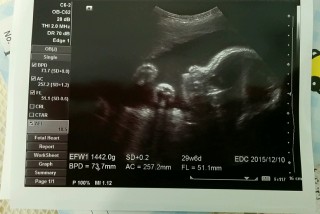

29w4d頭73.7㎜ お腹257.2㎜ 大腿骨51.1㎜ 体重1442g。 横顔が主人の寝顔に似てます(^^)d 前置胎盤が低置胎盤に!(*^^*) 喜んだのも束の間で、次の日出血があり入院になってしまいました。(現在入院中)張りが強かったようです。赤ちゃんは元気でほっとしてます。とにかく安静☆